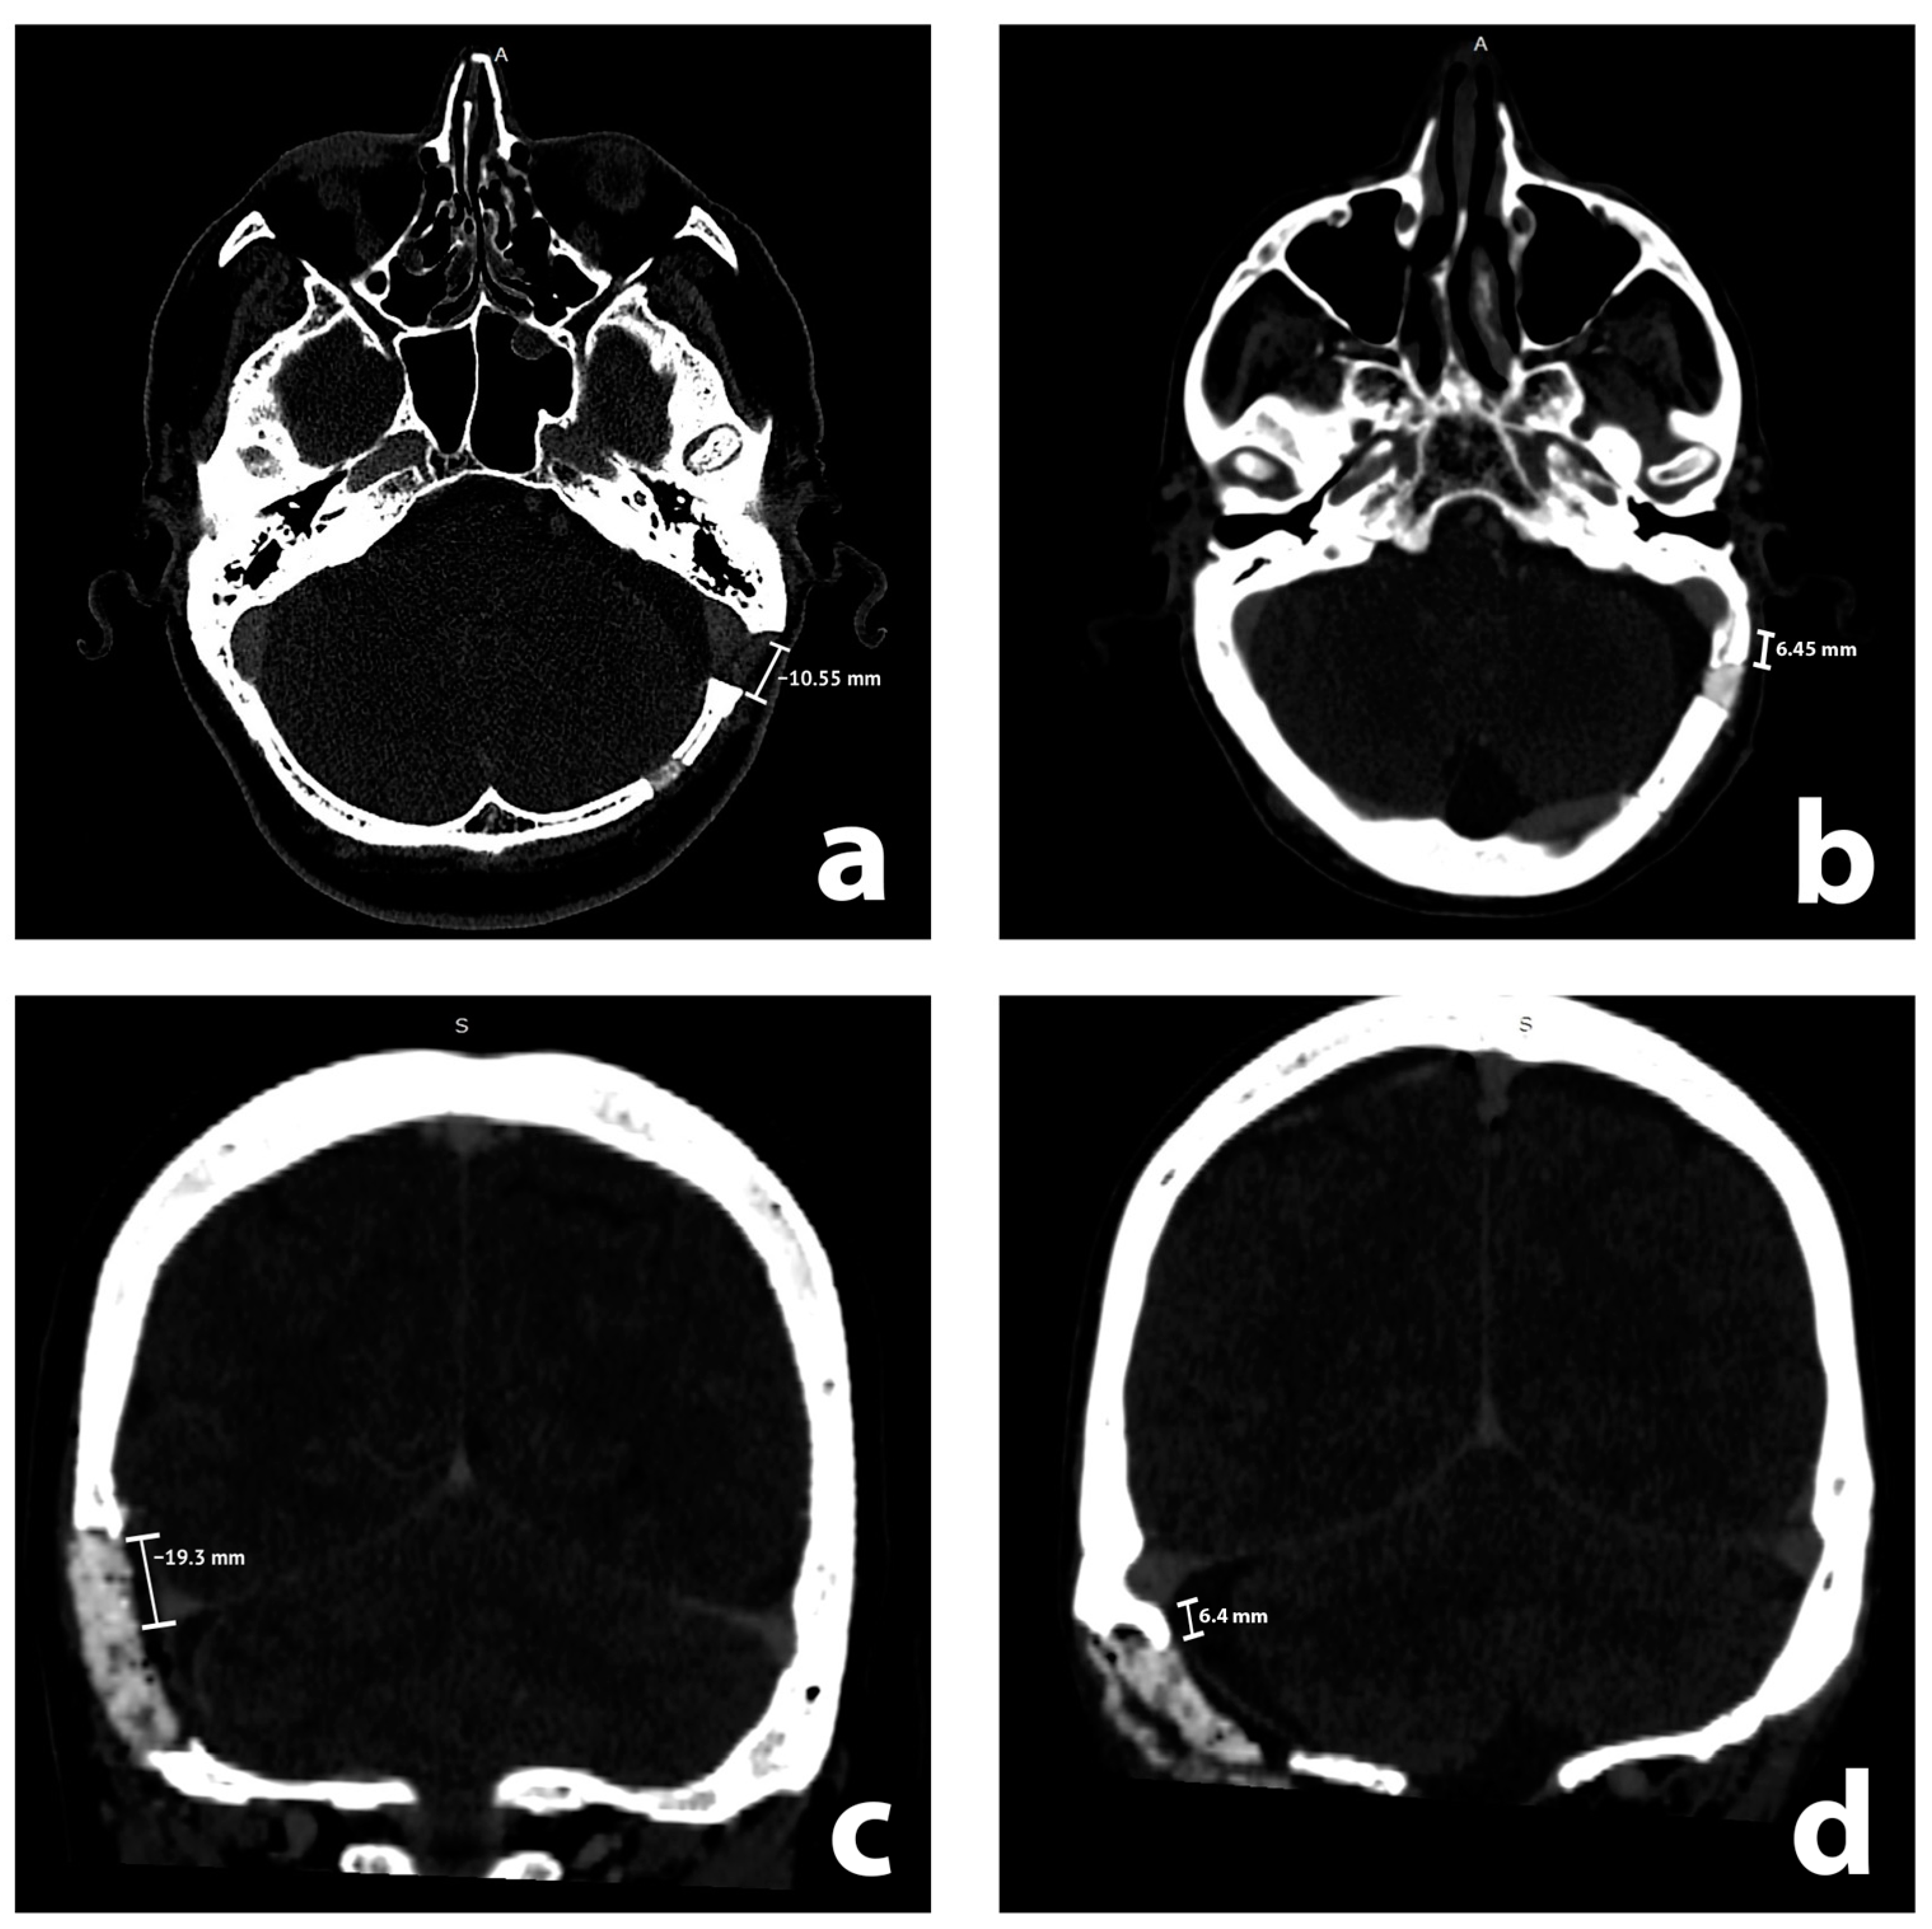

CT studies were reviewed by two teams, consisting of two neurosurgeons (attending and resident) and two medical students, all of whom were previously instructed by the attending neuroradiologist. We performed evaluations with GE software on radiological stations with diagnostic monitors. CT scans were evaluated for features of rCVST in the sigmoid sinus, transverse sinus, and their junction (each treated as a separate entity) on the ipsilateral side to the RSA. Recognizing rCVSTs required the visualization of a lack of contrast in the sinuses in postoperative CT scans. We considered intraluminal thrombi that partially or completely filled the sinuses as rCVST. Arachnoid (Pacchionian) granulations [9,10] were distinguished from rCVSTs by their distinctive, regular shape, in contrast to rCVSTs, which are irregular and often larger. We analyzed CT scans without any previous knowledge of the medical history of a patient or radiological report. We then reviewed the radiological reports of patients with rCVSTs, if these included descriptions of sinus thromboses. In addition, we evaluated the closest distance from the edge of the craniotomy to the sinuses on postoperative CT scans. It was measured and presented so that a positive value expressed the closest distance between the edge of the craniotomy and the sinus, whereas a negative value represented the magnitude of overlap of the craniotomy with the sinus (Figure 1). We performed such measurements for sigmoid and transverse sinus using axial and coronal scans, respectively. These continuous measurements were subsequently translated into qualitative evaluations of sinus exposure (which corresponded to all nonnegative measurements) and non-exposure of the sinus.

Figure 1. Illustrative radiological axial (a,b) and coronal (c,d) contrast enhanced postoperative computed tomography scans with measurements. Sigmoid and transverse sinuses are exposed in (a,c), while unexposed in (b,d), respectively.